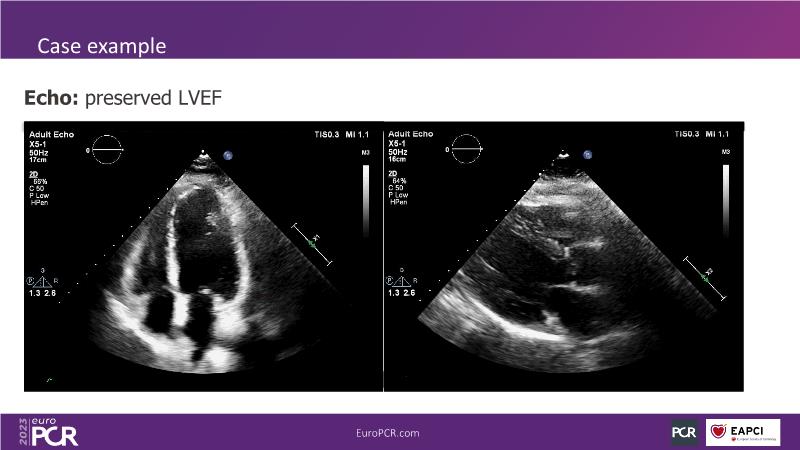

Explore angiography-based FFR/virtual FFR in this session. Uncover clinical evidence, identify ideal patients, and learn step-by-step integration into daily practice.

• To understand how to identify the patient who may benefit the most from its use